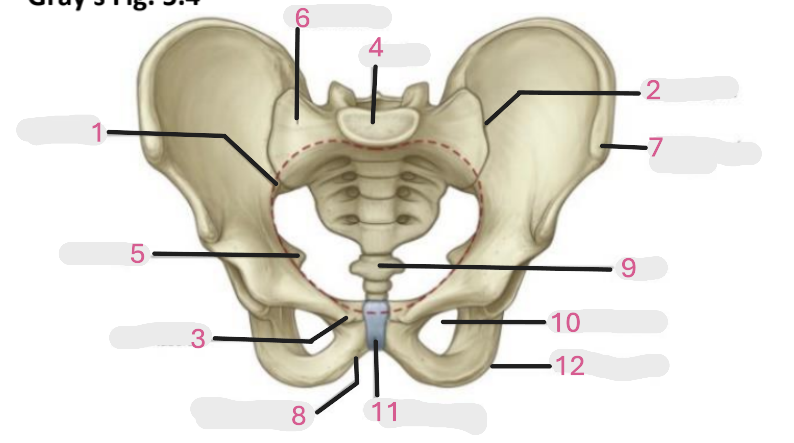

Where is the pelvic inlet

1

Where is the sacro-iliac joint

2

Where is the pubic tubercle

3

Where are the S1 body

4

Where is the ischial spine

5

Where is the ala of sacrum

6

Where is the anterior superior iliac spine

7

Where is the ischiopubic ramus

8

Where is the coccyx

9

Where is the obturator foramen

10

Where is the pubic symphysis

11

Where is the ischial tuberosity

12